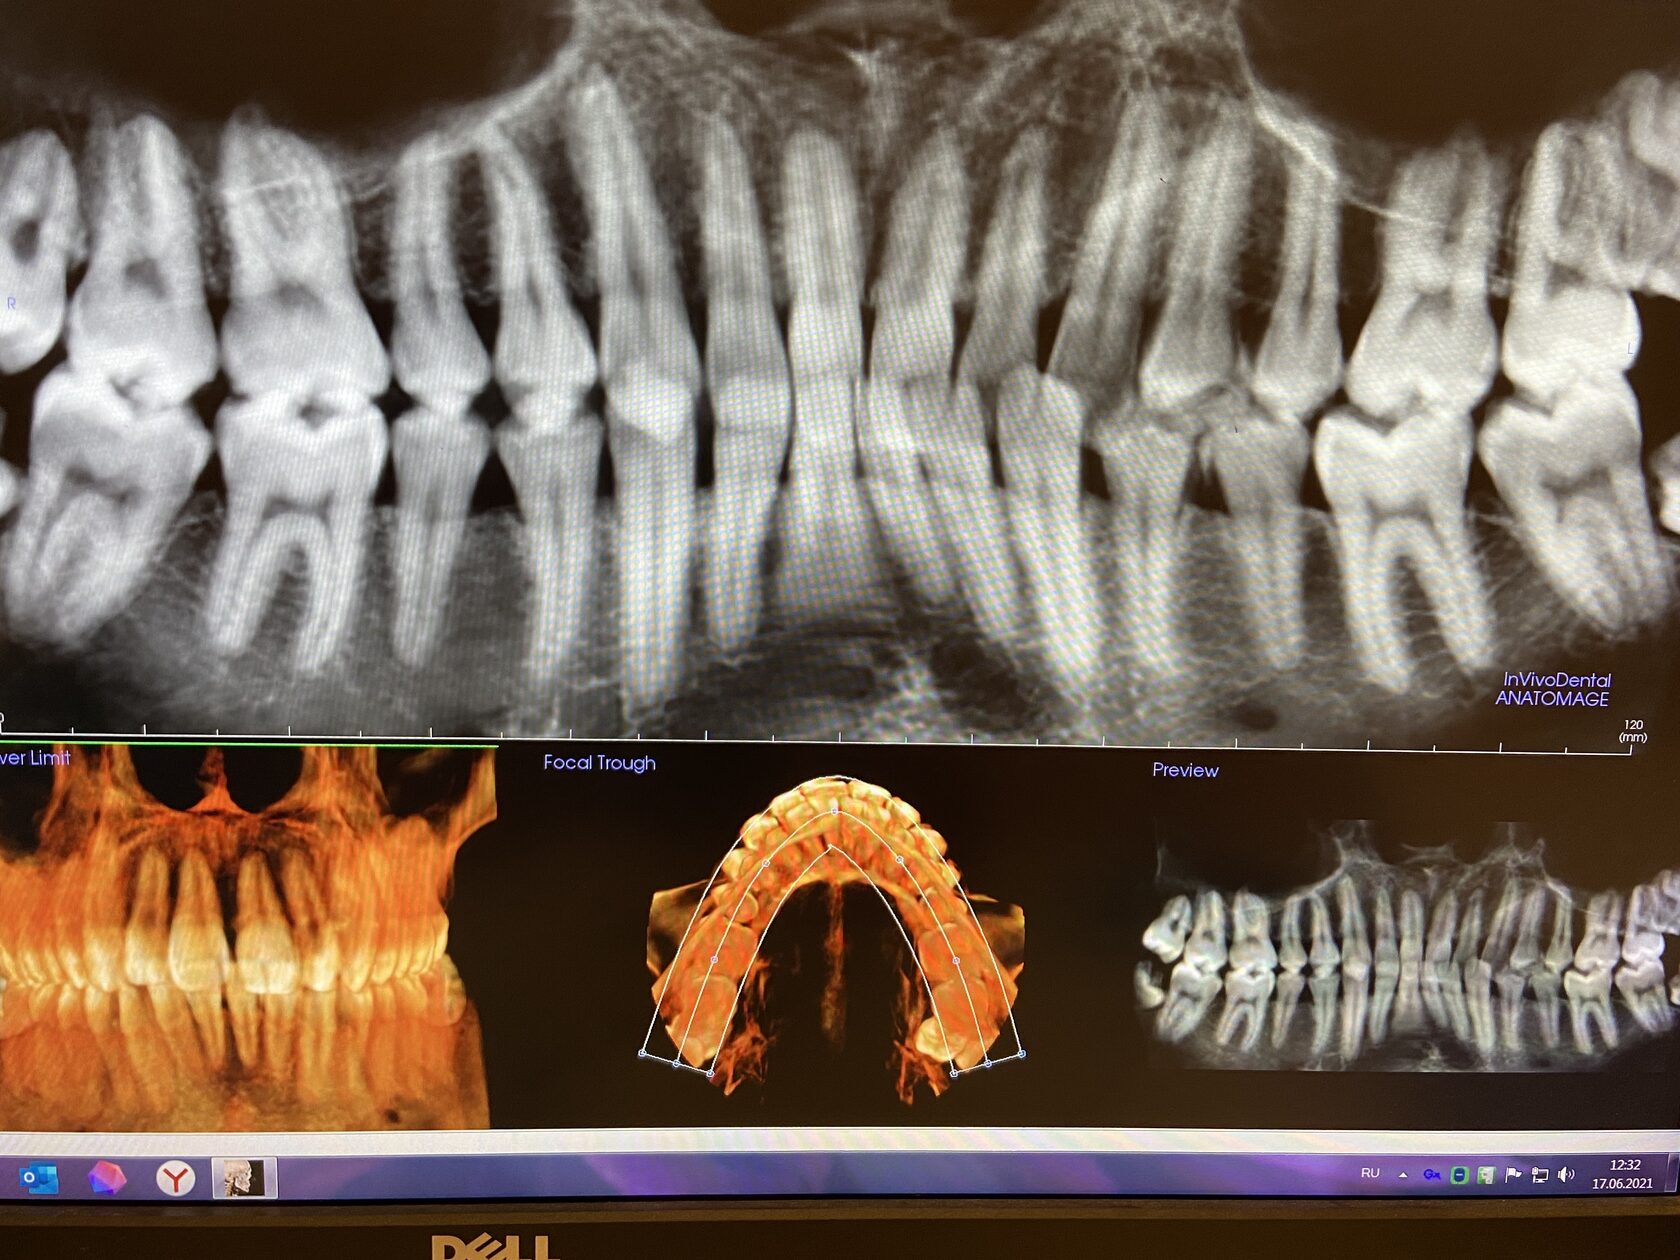

Фотографии ортопантомограмм и работ Родена